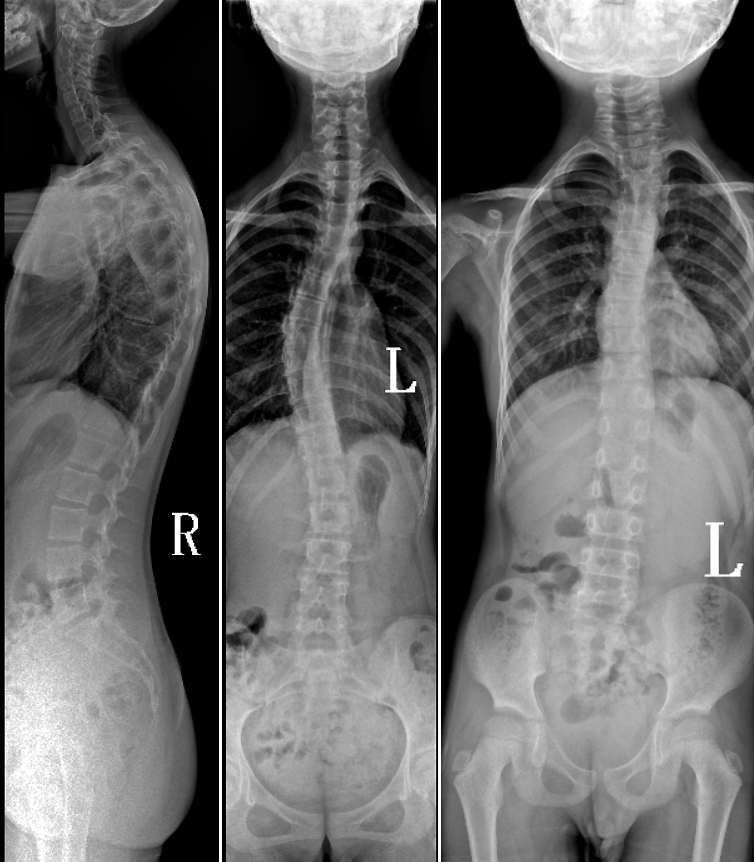

DR是臨床骨科的重要檢查手段之一。在骨科檢查中,脊柱矯形、長(zhǎng)骨骨折、腰椎退行性病變等,需要采集脊柱、下肢全景圖像,輔助醫(yī)生臨床診斷,從而制定科學(xué)的治療方案,普愛醫(yī)療的大視野平板動(dòng)態(tài)DR就像是一座橋梁,連接起現(xiàn)代醫(yī)療技術(shù)與當(dāng)?shù)厝嗣竦尼t(yī)療需求。

普愛醫(yī)療自主研發(fā)的大視野平板動(dòng)態(tài),采用17"*34"的有效視野,一次曝光即可得到全脊柱或全下肢影像。相較于多張攝影再軟件拼接的DR設(shè)備,PLX8600解決了拼接圖像存在密度不均勻,拼接處圖像配準(zhǔn)和放大效應(yīng)等問題,給臨床帶來了真正的大視野影像解決方案。

除了常規(guī)靜態(tài)攝影外,PLX8600的大平板具備動(dòng)態(tài)透視和點(diǎn)片功能,能夠很好地觀察復(fù)雜部位病灶,有效地抓取關(guān)鍵幀,降低患者多次攝片的概率。如:全脊柱狀態(tài)評(píng)估、長(zhǎng)骨關(guān)節(jié)活動(dòng)度、下肢靜脈造影瓣膜功能評(píng)估、消化道功能評(píng)估、脊髓造影等更多大視野臨床應(yīng)用,“多面手”都能輕松應(yīng)對(duì)。